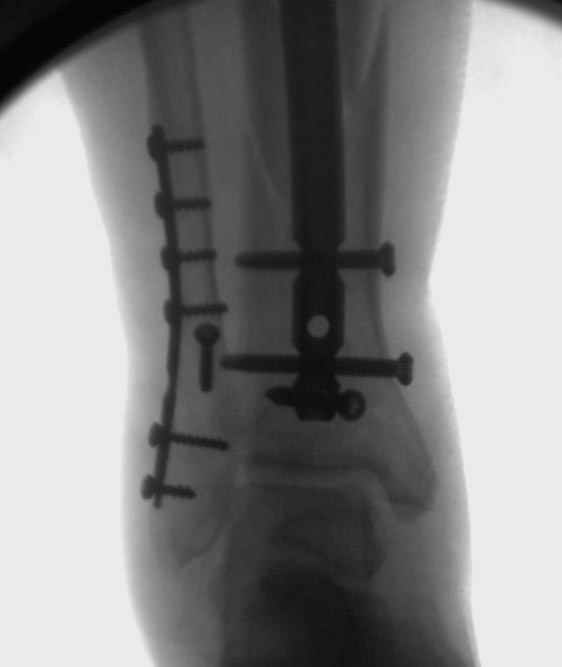

У меня молодой врач на линии, снимки отправил через эл. почту,

спрашивает что делать с больным который поступил недавно, фермер 55 лет падение при пьяной драке в баре, года два назад перенес операцию на лодыжке, на снимках и КТ перелом без вовлечения сустава,

Повреждение такой локализации, на которой применимы и аппарат (классический Илизарова или гибридный), пластина, особенно Locked Plate, и гвоздь с блокированием. В нашей клинике был бы выполнен закрытый интрамедуллярный остеосинтез. Желательно использовать гвоздь с возможностью провести более чем 2 обычных фронтальных винта в дистальном отломке.

Здесь мы использовали новый Synthes Nail с дополнительными дырками, в проксимальной части 4: по две косых и поперечные (один стандартный а другой динамический), в дистальной части две поперечные, прямая и косая. Вес больного более 120 кг, нагрузку начнем через месяц.

Получилось красиво, поздравляю. Вверху можно было ограничиться одним винтом во фронтальное статическое отверстие, зачем два 45-градусных?

При такий спирали задний край tibia может быть сломан - нет ли этого в данном случае? На всякий случай можно было ввести 1-2 винта 4,5 мм спереди назад мимо гвоздя. Хотя самый дистальный блокирующий винт, возможно, зацепил этот отломок. А какой тут диаметр гвоздя и locking винтов?